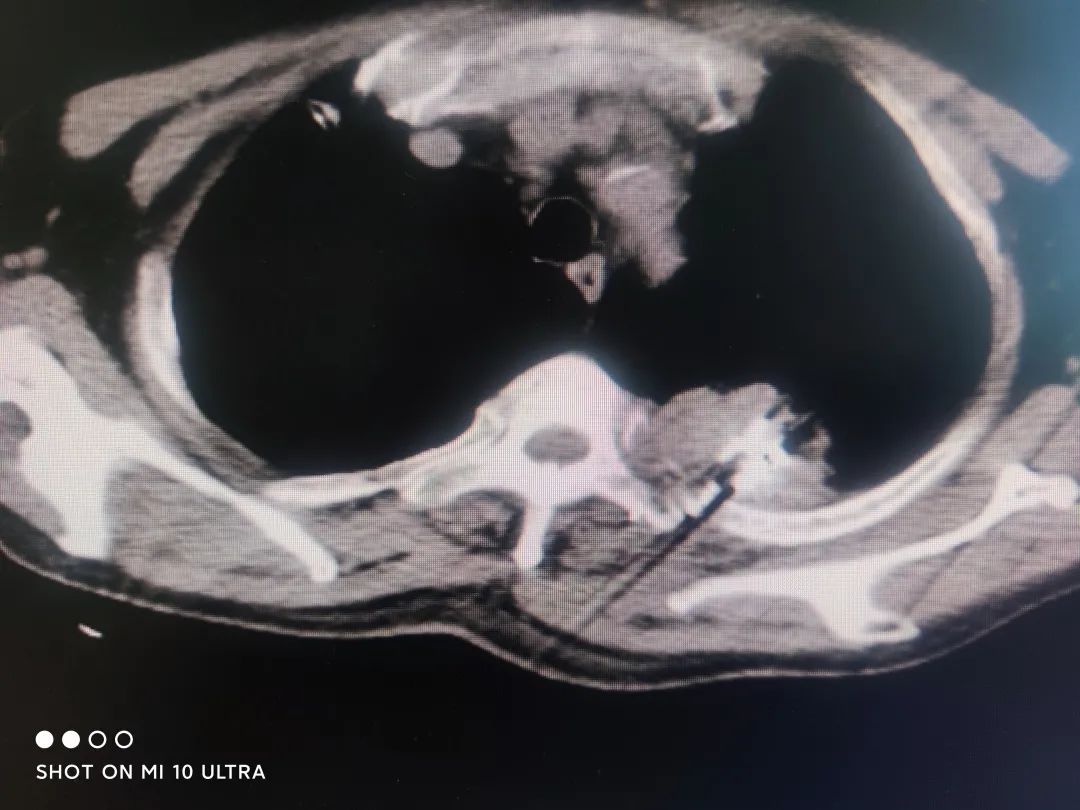

“ 不开刀就能消灭恶性肿瘤,真没想到小小的碘粒子,竟有如此大的威力,感谢广东药科大学附属第三医院肿瘤科一区的专家团队,为我做了粒子植入术,解除了我的痛苦。 ” 就在两个月前, 63 岁的陈女士在我院接受了 CT 引导下放射性碘 125 粒子经皮组织间植入术,术后效果良好,同时配合中医治疗,不仅疼痛减轻,而且肿瘤明显缩小,病情得到有效控制。

近年来,我国癌症发病率和死亡率不断上升,而放射性粒子对恶性肿瘤细胞的靶向近距离*伤杀**,在肿瘤治疗领域越来越受到关注。放射性碘125粒子可以通过微创 ( 经皮穿刺 ) 方法植入肿瘤或转移病灶,在碘 125 粒子衰变过程中,发射低剂量 γ 射线对肿瘤组织进行持续照射,可以杀死不同时期已经裂变的肿瘤细胞,有效治疗肿瘤,防止肿瘤复发和转移。其中碘 -125 粒子的辐射范围只有左右,大部分能量被肿瘤组织吸收,对周围正常组织的损伤很小。